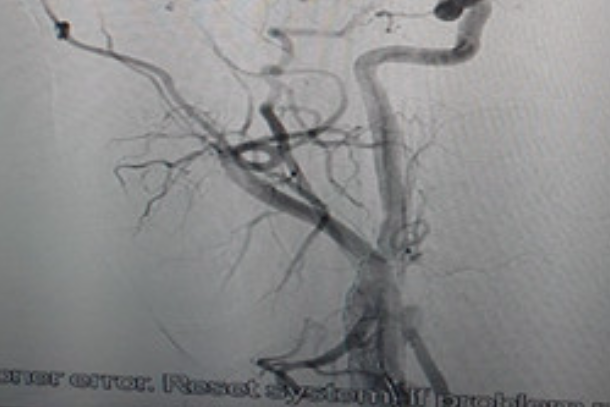

Hình ảnh gốc động mạch cảnh trong phải bị tắc (trái) và tái thông hoàn toàn sau can thiệp (phải). Ảnh: BVCC

Ngay lập tức, bệnh nhân được bác sĩ Trung tâm Đột quỵ chỉ định điều trị bằng phương pháp can thiệp lấy huyết khối động mạch não bằng dụng cụ cơ học, đặt stent động mạch cảnh gốc. Thời gian can thiệp khoảng 30 phút cho kết quả tái thông hoàn toàn.